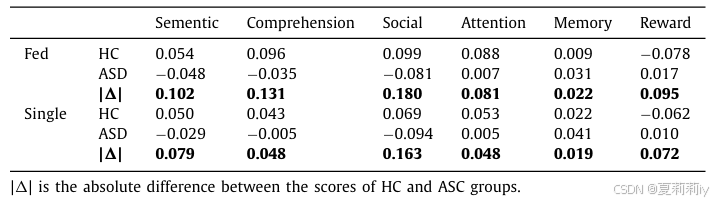

2.5.4. Evaluate model from interpretation perspective

(3)Neural patterns: Connectivity in the autistic brain

①They define "informativity" as functional representation difference between ASD and HC groups and "robustness" as the biomarker consistency of 4 sites

②They applied guided back-propagation method to detect the robust biomarkers of HC in Fed:

③ASD biomarker:

④Function correlation:

2.5.5. Limitation and discussion